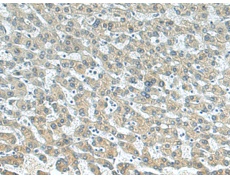

IHC positive control: |

Human liver cancer |

IHC Recommend dilution: |

100-200 |